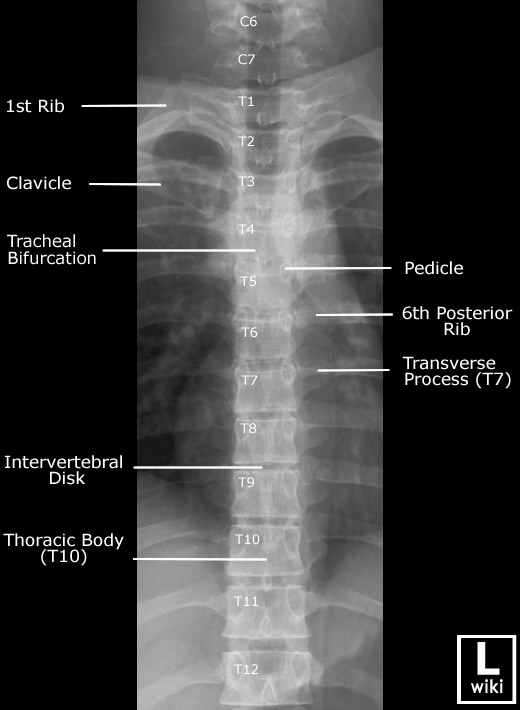

Spine Radiographic Anatomy

| AP view (Cervical) | AP view (Thoracic) |